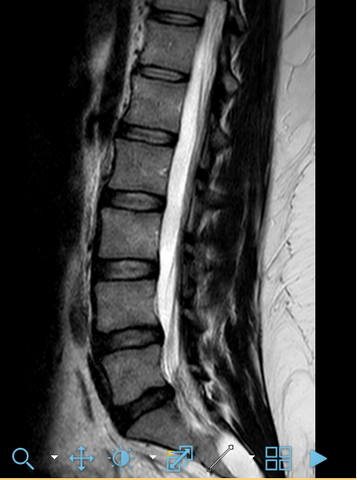

Mrt Bild Lendenwirbelsaule Bandscheibe Hat Jemand Ahnung Gesundheit Und Medizin Ruckenschmerzen Bandscheibenvorfall Lws